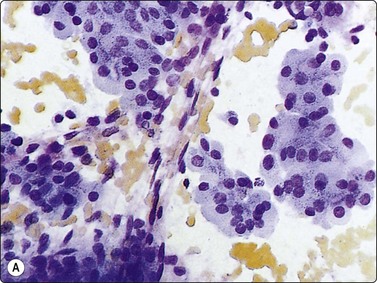

image image

Fig. 6.18 Follicular neoplasm

Cellular smears of single cells, microfollicles or rosettes in a repetitive manner; benign adenoma by histology (A, MGG, HP; B, Pap, HP).

Fig. 6.19 Follicular neoplasm

Smears very similar to Figure 6.18; follicular carcinoma with vascular invasion by histology (A, MGG, HP; B, Pap, HP).

Smears in FN are cellular in a bloody background that is usually devoid of colloid. Many uniform-sized follicular cell clusters, microfollicles and rosette formations are present. Syncytial aggregates, nuclear crowding and overlapping are also often seen.

The repetitive smear pattern with uniform cell population is in contrast to the variable pattern of different cell types seen in colloid and hyperplastic nodules. Microacinar clusters with a central lumen (that may contain a drop of colloid) represent microfollicles (Figs 6.18, 6.19 and 6.21B). These are characteristic of FN but may be found focally in NG. Rosette-like groupings without a lumen (Fig. 6.20) suggest a more solid growth pattern. A trabecular pattern is represented by rows and elongated aggregates of epithelial cells that resemble papillary structures when they adhere to strands of vascular stroma (see Fig. 6.33B,C). Small blood vessels with adherent epithelial cells can be found in any type of follicular neoplasm (see Fig. 6.25A).